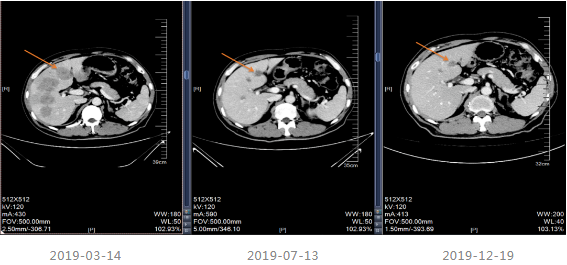

2019-03-21至2019-09-02采用化疗+靶向进行治疗,治疗11周期,第1周期采用FOLFIRI方案,第2-11周期FOLFIRI+西妥昔单抗。

治疗期间于2019-07-13及2019-12-19进行疗效评估,疗效评价PR,建议患者切除原发灶,患者拒绝。CEA、CA199降至正常范围。